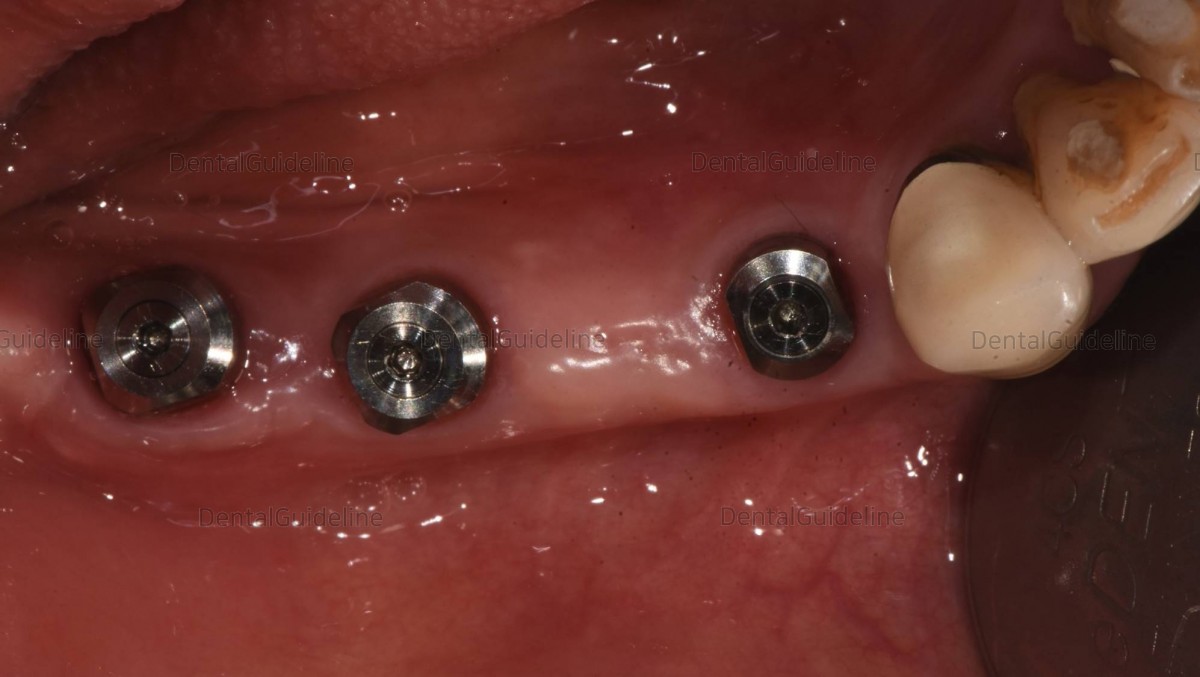

Final-sized healing abutments were engaged to the fixture after gradual

expansion using the serial size of the healing abutment on the day of the implant 2nd surgery and ISQ

reading.

4 days after the implant second surgery.